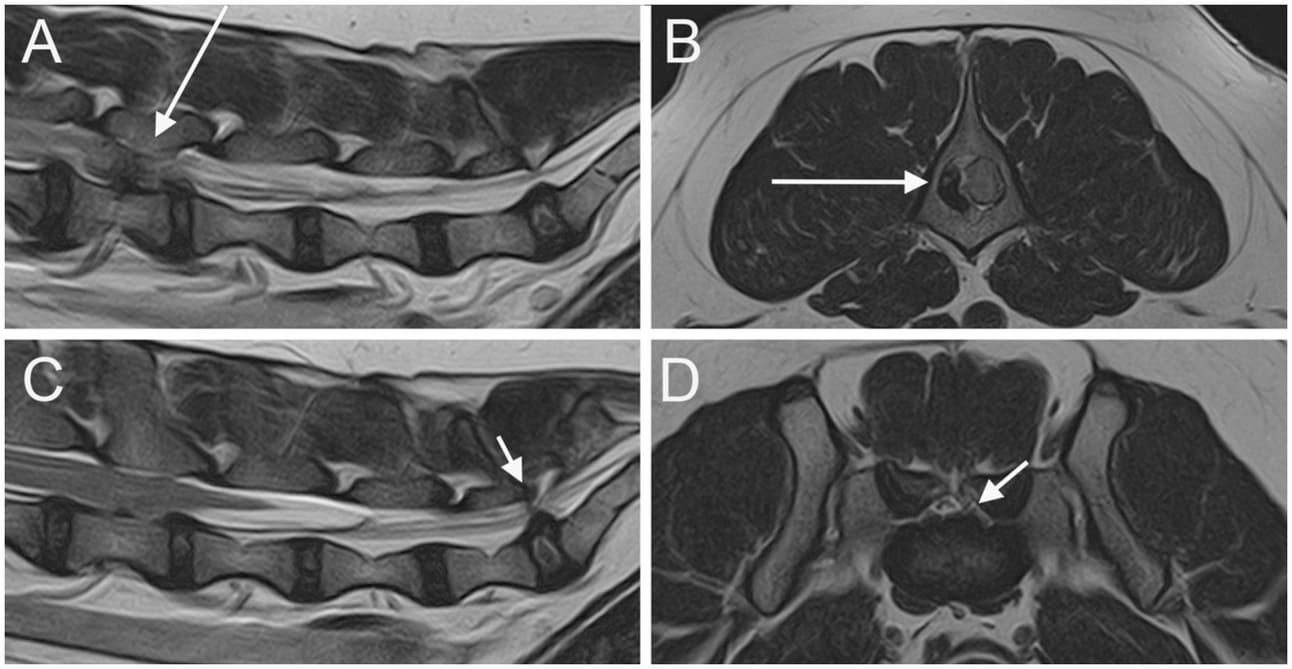

Parasagittal (A) and sagittal (C) T2W images of the lumbar vertebral column and the LS junction; transverse T2W at the level of L4 vertebra (B) and at the level of LS junction (D). A severe extrusion of the L4-L5 IVD in seen on the right side of the vertebral canal (long arrow). An IVDP affecting both the vertebral canal and the intervertebral foramina is seen at the LS junction (short arrows).